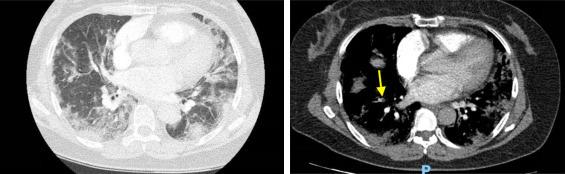

The Coronavirus disease-2019 outbreak (COVID-19) has been declared a pandemic by the World Health Organization. Studies report both a severe inflammatory syndrome and a procoagulant state in severe COVID-19 cases, with an increase of venous thromboembolism, including pulmonary embolism (PE) and deep vein thrombosis (DVT). In this context, we discuss the use of doppler ultrasonography (DUS) in the screening and diagnosis of DVT in ambulatory and hospitalized patients with, or suspected of having, COVID-19, outside the intensive care unit (ICU).

In patients hospitalized for or suspected of COVID-19 infection with the presence of either (a) DVT clinical symptoms, (b) a strong DVT clinical probability (Wells score>2) or (c) elevated D-dimer levels without DVT clinical symptoms and without PE on lung CT angio-scan, DVT should be investigated with DUS. In the presence of PE diagnosed clinically and/or radiologically, additional systematic DVT screening using DUS is not recommended during the COVID-19 pandemic. The use of 4-points compression DUS for DVT screen and diagnosis is the most appropriate method in this context.

世界卫生组织已宣布2019冠状病毒病疫情(COVID-19)为大流行。研究报告称,重症COVID-19病例存在严重炎症综合征和促凝状态,静脉血栓栓塞症增加,包括肺栓塞(PE)和深静脉血栓形成(DVT)。在此背景下,我们讨论在非重症监护病房(ICU)的门诊和住院COVID-19患者或疑似患者中,使用多普勒超声检查(DUS)筛查和诊断DVT的情况。

对于因COVID-19感染住院或疑似感染的患者,若存在以下情况之一:(a)DVT临床症状;(b)DVT临床高度可能性(Wells评分>2);或(c)D-二聚体水平升高但无DVT临床症状且肺部CT血管造影未发现PE,则应用DUS对DVT进行检查。在临床和/或影像学诊断为PE的情况下,不建议在COVID-19大流行期间使用DUS进行额外的系统性DVT筛查。在这种情况下,使用四点压迫DUS进行DVT筛查和诊断是最合适的方法。